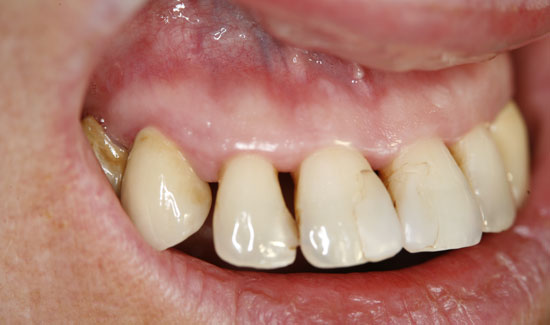

Fig. 2: Clinical aspect of region 12, formation of gas bubbles on the inflamed tissue. Continuous suction in the vicinity of the area of use